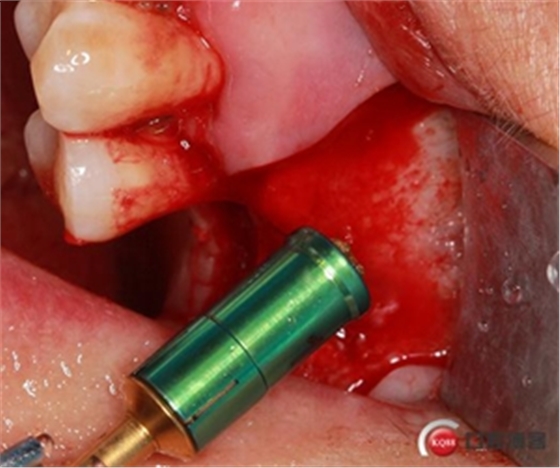

開孔鉆上安裝1mm停止環(huán)。

開窗位置鉆入1mm深度,未能穿透骨壁。

更換2mm停止環(huán)。

穿透上頜竇頰側(cè)骨壁,由于擴孔鉆鉆頭特殊的設(shè)計形態(tài)

轉(zhuǎn)速雖快但不會穿破上頜竇膜。

使用水壓系統(tǒng),將1ml左右生理鹽水緩慢注入開孔內(nèi)。